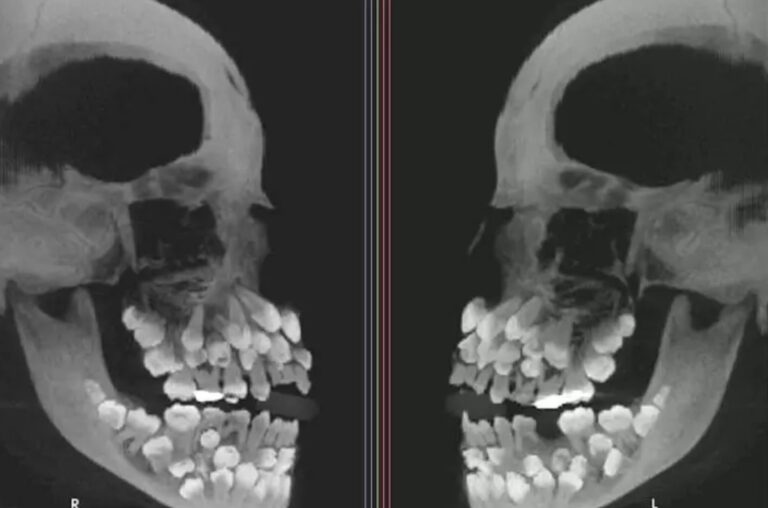

Una niña de 11 años en Brasil ha desconcertado a la comunidad científica con su caso de hiperdoncia múltiple, una condición que hace que los dientes broten en mayor cantidad y en diferentes lugares de la boca. La niña debería tener 28 dientes, pero después de una radiografía, los especialistas descubrieron que tenía 81.

Según un informe de La Vanguardia, 18 de los dientes eran de leche, 32 permanentes y 31 múltiples, que son los que obedecen a la condición mencionada anteriormente. La hiperdoncia puede estar asociada con otras condiciones como labio leporino o displasia cleidocraneal y puede causar malposiciones dentales, problemas a la hora de masticar, riesgo de caries y patologías en las encías.